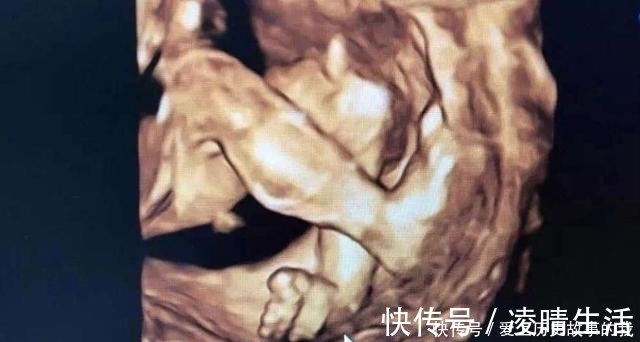

四维检查是对胎儿的各项器官进行排畸筛查,医生通过彩超仪器来观察胎儿的发育情况、胎盘、羊水等,还可以打印出比较清晰的胎儿面部图片,孕妈可以看到腹中孩子的大致长相。很多宝爸宝妈第一次看到宝宝如此清晰的照片,很激动,也顾不上看产检单上的其他数据,就只盯着照片看。其实,四维产检单出来之后,除了看宝宝的照片,其他数据一样要仔细看看。

【 宝宝|四维彩超,孕妈们最期待的产检,除了看宝宝的照片还需要看什么?】四维彩超是可以比较清晰的看到孩子的四肢和颜面部的发育情况的,如果孩子有兔唇四肢畸形是可以发现的。